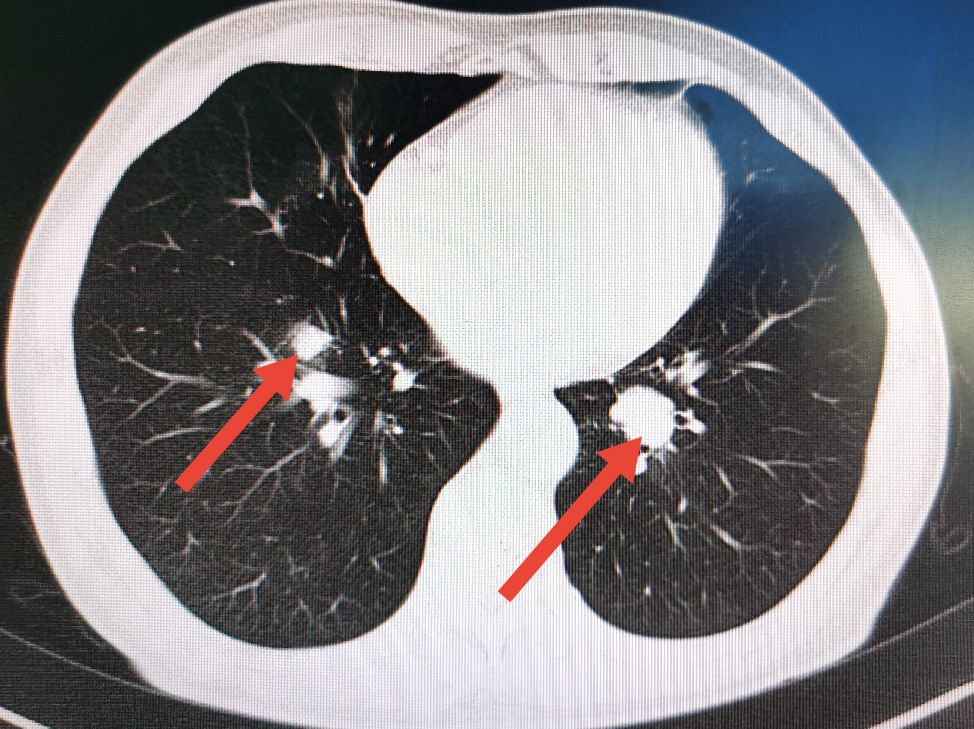

术后一年半的时候,常规复查时发现病人双肺出现明确的转移病灶,但患者一般情况及营养状况比术前有所好转,随后给予联合化疗和靶向药物治疗。

肺部CT显示左右肺均有转移病灶